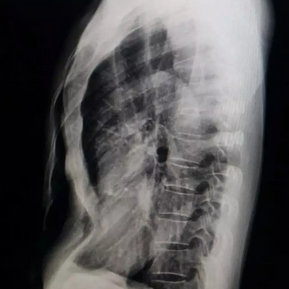

The patient is a 59-year-old male who has had a sunken chest since childhood, and the depression worsened gradually after adolescence. From the age of 30, he began experiencing chest tightness, which became more pronounced during vigorous activities. Three years ago, the patient underwent surgery to remove a cyst from his left lung, during which a rib from the left chest wall was removed, but no treatment was done for the pectus excavatum. Over the past two years, his symptoms have significantly worsened, leading to chest tightness, breathlessness, and difficulty breathing even at rest.

The anterior chest wall exhibits an obvious depression, causing severe compression and displacement of the heart to the left thoracic cavity. The Haller index is notably high at 5.6.